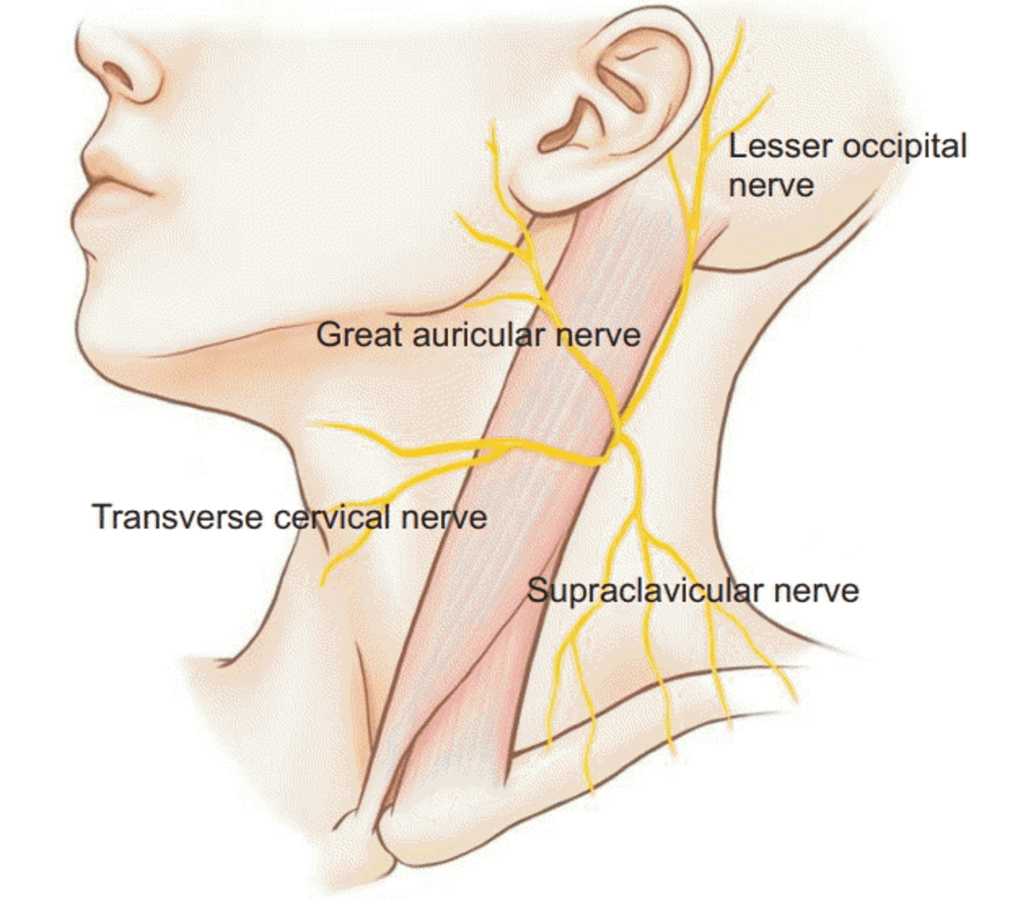

Cervical Plexus (C1-4)

Superficial Cutaneous Cervical Plexus

Lesser occipital nerve

Greater auricular nerve

Transverse cervical nerve

Supraclavicular nerve